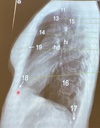

Que estructura anatómica esta en el numero 11

Traquea

41

Que estructura anatómica esta en el numero 13

Vasos supra aórticos

42

Que estructura anatómica esta en el numero 15

Espacio retro traqueal

43

Que estructura anatómica esta en el numero 9

Cayado aórtico

44

Que estructura anatómica esta en el numero 14

Espacio aéreo retro-esternal

45

Que estructura anatómica esta en el numero 19

Esternón

46

Que estructura anatómica esta en el numero 18

S.Cardiofrenico